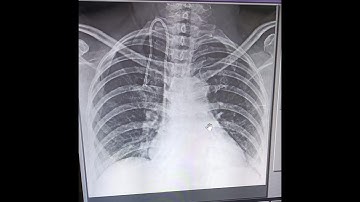

Insertion of a totally implantable vascular access device (TIVAD)